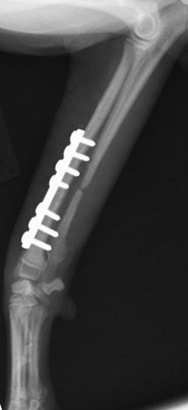

両前肢の骨折:橈骨尺骨骨折整復手術①

<右前肢>

![]() 来院時の右橈骨尺骨骨折のレントゲン写真 |

![]() 手術後のレントゲン写真 |

手術写真です。骨折端を露出させ、骨折端を合わせて、プレートとスクリューにて固定します。 |